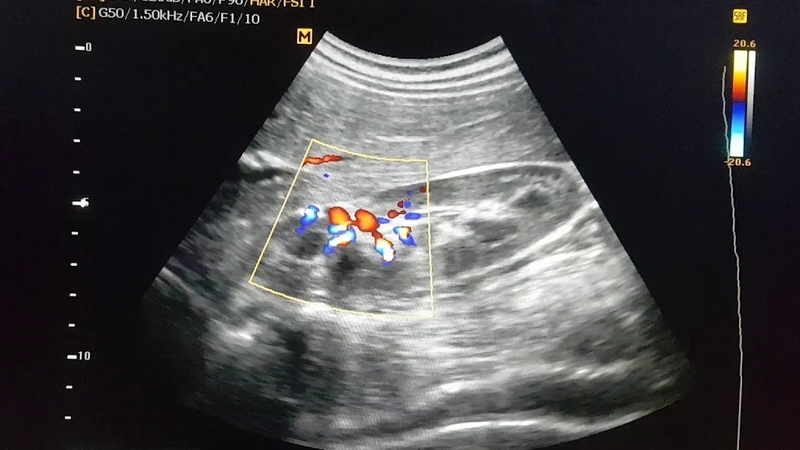

Siêu âm sỏi thận là một quy trình chẩn đoán giúp đánh giá kích thước, hình dáng và vị trí của thận, đồng thời giúp chẩn đoán tình trạng sỏi thận. Vậy thực hiện siêu âm sỏi thận cung cấp cho bác sĩ những thông tin? Có nên siêu âm sỏi thận không? Hãy cùng nhà thuốc Long Châu tìm hiểu về siêu âm sỏi thận trong bài viết sau nhé.

Siêu âm sỏi thận (hay còn gọi là siêu âm thận) sử dụng sóng âm thanh để tạo ra hình ảnh, từ đó giúp chẩn đoán các vấn đề liên quan đến thận.

Hình ảnh siêu âm được tạo ra nhờ sử dụng sóng âm thanh truyền qua các mô của cơ thể, âm thanh được ghi lại và chuyển thành ảnh trắng đen. Quá trình siêu âm không gây ra đau đớn cho người bệnh.